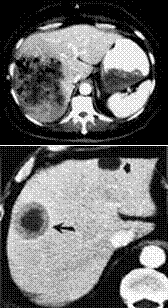

Trong những vùng lưu hành bệnh, người thường xuyên bị nhiễm bởi F. hepatica. Hai giai đoạn đã được mô tả theo khía cạnh lâm sàng của bệnh sán lá gan lớn ở người. Giai đoạn đầu tiên liên quan đến quá trình xâm nhập nhu mô gan. Trong quá trình giai đoạn thứ 2, hay còn gọi là pha hệ đường mật và khi đó ký sinh trùng tiếp tục nằm trong đường mật nhiều năm nữa. CT là một công cụ hữu ích trong chẩn đoán bệnh sán lá gan lớn giai đoạn xâm nhập. Nếu các tổn thương đặc trưng được nhìn thấy đi kèm với tình trạng tăng bạch cầu ái toan thì có lẽ chẩn đoán nhiễm sán F. hepatica là có thể. Một số trường hợp có biến chứng trên lâm sàng hoặc các đặc điểm không điển hình cho một ca bệnh cũng đã được báo cáo trong thời gian gần đây. Điều thú vị về bệnh nhân này là hình ảnh CT biểu hiện một tổn thương rất lớn với một ổ xuất huyết hoại tử dưới bao gan mà theo họ chưa bao giờ gặp ở những ca bệnh trước đây.

Trong giai đoạn xâm nhập, sán di chuyển khắp nhu mô gan và vào trong đường mật và sẽ quy kết các thay đổi về tỏn thương bệnh học do sán lá gan lớn. Không giống như những tổn thương riêng rẻ trên những cá nhân có liên quan đến các absces sinh mủ, các microabsces ở gan gây ra do F. hepatica không kết hợp thành một nhóm (coalesce) là khoang abces lớn. Chúng có xu hướng không gia tăng kích thước và nói chung phát triển chậm. Sự khác biệt giữa abces gan do vi khuẩn sinh mủ và các tổn thương gan do sán lá gan có thể giải thích theo hình ảnh của tổn thương do sán, có các hình ảnh hoại tử hơn là quá trình sinh mủ.

F.hepatica phải đi xuyên qua bao gan Glisson từ khoang phúc mạc vào nhu mô gan. Do đó, bất kỳ khi nào gan bị liên quan, bao gan và vùng nhu mô gần bao gan cũng luôn luôn bị ảnh hưởng. 2 loại tổn thương gan và vùng dưới bao gan biểu hiện rõ có thể nhìn thấy rõ trên hình ảnh CT.

Loại tổn thương thứ 2 đặc hiệu hơn, loại tổn thương có hình ảnh giảm âm (hypodense), với các đường ngoằn nghoèo như hình con rắn trên phim chụp CT. Sự xuất hiện trên CT các hình ảnh bao gan dày và nhu mô gan giảm nhiều cũng được mô tả như thể hình ảnh CT của bệnh sán lá gan lớn đặc trưng. Một hình ảnh tụ máu dưới bao gan lớn đơn thuần sẽ không đặc trưng cho bệnh sán lá gan lớn. Một hình ảnh tụ máu dưới bao gan có xuất huyết có thể là một biến chứng trong giai đoạn sán xâm nhập. Trong trường hợp hiếm, chảy máu có thể đe dọa tính mạng bệnh nhân vì độ trầm trọng và khả năng chảy máu tái phát. Sự liên quan của u máu dưới bao gan kèm theo tăng bạch cầu ái toan tăng cao sẽ đề nghịhoặc là viêm đa động mạch nút (polyarteritis nodosa) hoặc sán lá gan giai đoạn xâm nhập. Trong giới hạn với sự hiểu biết của nhóm nghiên cứu, một tổn thương dưới bao gangây ra bởi sán lá gan lớn gây abces dường như hiếm khi được báo cáo trong y văn.